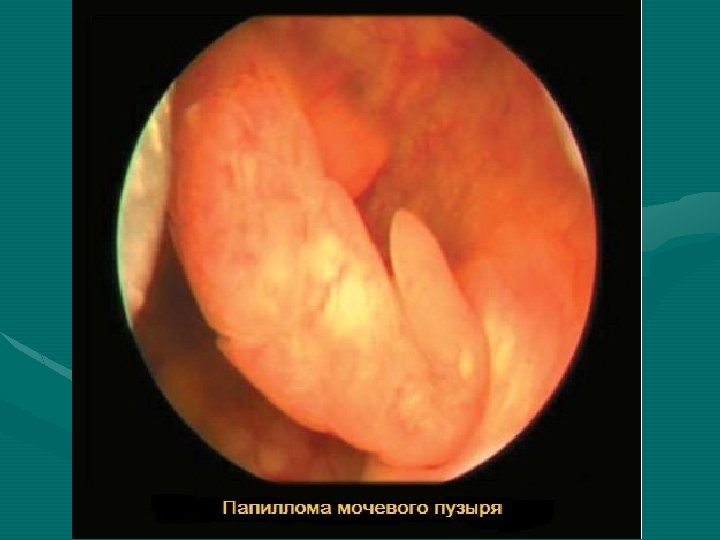

Предрак В большинстве случаев рак мочевого пузыря развивается на фоне предраковых процессов (атипичная гиперплазия, дисплазия слизистой оболочки) и доброкачественных опухолей (папиллома).

Патогистологические варианты рака мочевого пузыря Патоморфология. 1. 2. 3. Переходноклеточная (паппилярная) карцинома – 90 -95 % Плоскоклеточный рак – 3 -5 % Аденокарцинома – 2 %

• • • Диагностика Стандартным методом диагностики опухолей есть цистоскопия и биопсия опухоли. Цистоскопия Биопсия ткани опухоли мочевого пузыря Цитологическое исследование осадка мочи Сложные методы диагностики (комп’ютерная томография, УЗИ) Процедура проведения цистоскопии

На фотографии слева: сгустки крови из опухоли. Справа показаны нежные сосочковые разростания экзофитного процесса. Карцинома.